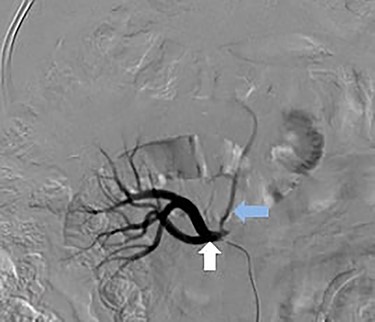

A 66-year-old male was referred to our institution for management of a liver lesion found incidentally on abdominal imaging. There was no significant past medical or surgical history, and he was asymptomatic. On physical examination, the patient was vitally stable and all systemic examinations were unremarkable. Contrast-enhanced triple phase abdominal computed tomography (CT) scan showed an arterial enhancing lesion in Segment I of liver with early washout, consistent with HCC (Fig. 1). This lesion received blood supply from the right renal artery (Fig. 2). Ultrasound-guided biopsy was performed to confirm the diagnosis of HCC, and subsequently the patient successfully underwent TACE. Figures 3 and 4 show the angiographic findings of the right renal artery branch supplying the lesion. Repeat CT scan at 6-week follow-up showed no evidence of residual disease.

Selective catheter angiogram of right renal artery (white arrow) showing a branch near its origin (blue arrow) supplying the hepatic lesion.